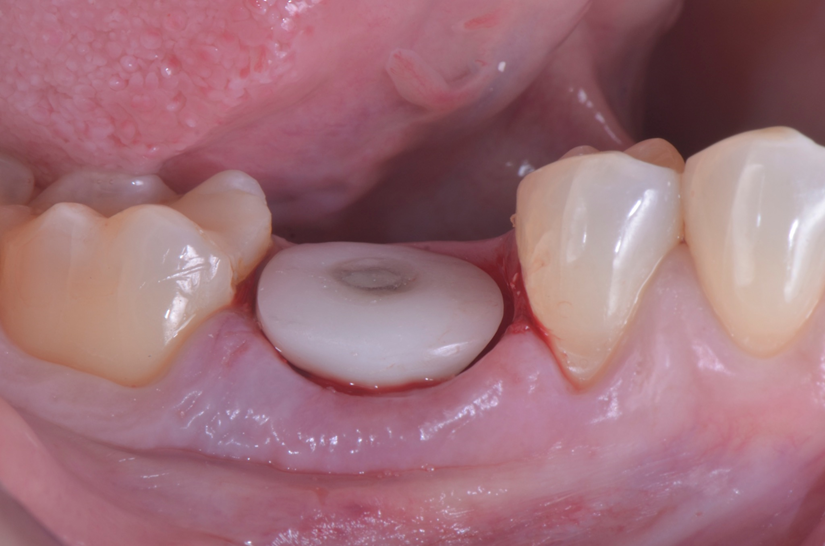

O paciente apresentou fratura vertical mésio-distal no elemento 46. Foi planejada a exodontia minimamente traumática e instalação imediata do implante Maestro Superiore (Implacil Osstem) utilizando uma guia prototipada. Após a exodontia, o implante foi instalado seguindo o protocolo de cirurgia guiada. O GAP vestibular foi preenchido com o Extra Graft. Um cicatrizador personalizado impresso com haletas facilitadoras foi capturado com resina flow e instalado. Após 30 dias, foi realizado escaneamento indireto para obtenção do perfil de emergência, utilizando protocolo digital com sobreposição do cicatrizador escaneado para confecção da coroa definitiva em zircônia policristalina estabilizada por ítria.

O uso de cicatrizadores personalizados, especialmente confeccionados por impressão 3D, tem ganhado destaque por permitir a conformação tecidual progressiva, facilitando a reprodução do perfil de emergência no fluxo digital6,7. A captura do cicatrizador com haletas de retenção com resina flow e seu posterior escaneamento são etapas críticas para assegurar a fidelidade da transferência do perfil de emergência e garantir um planejamento restaurador mais previsível8.

Neste caso, a sobreposição digital entre o cicatrizador escaneado e o desenho da coroa possibilitou comparar perfis de emergência com excelente adaptação clínica, contribuindo para um resultado estético e funcional adequado.